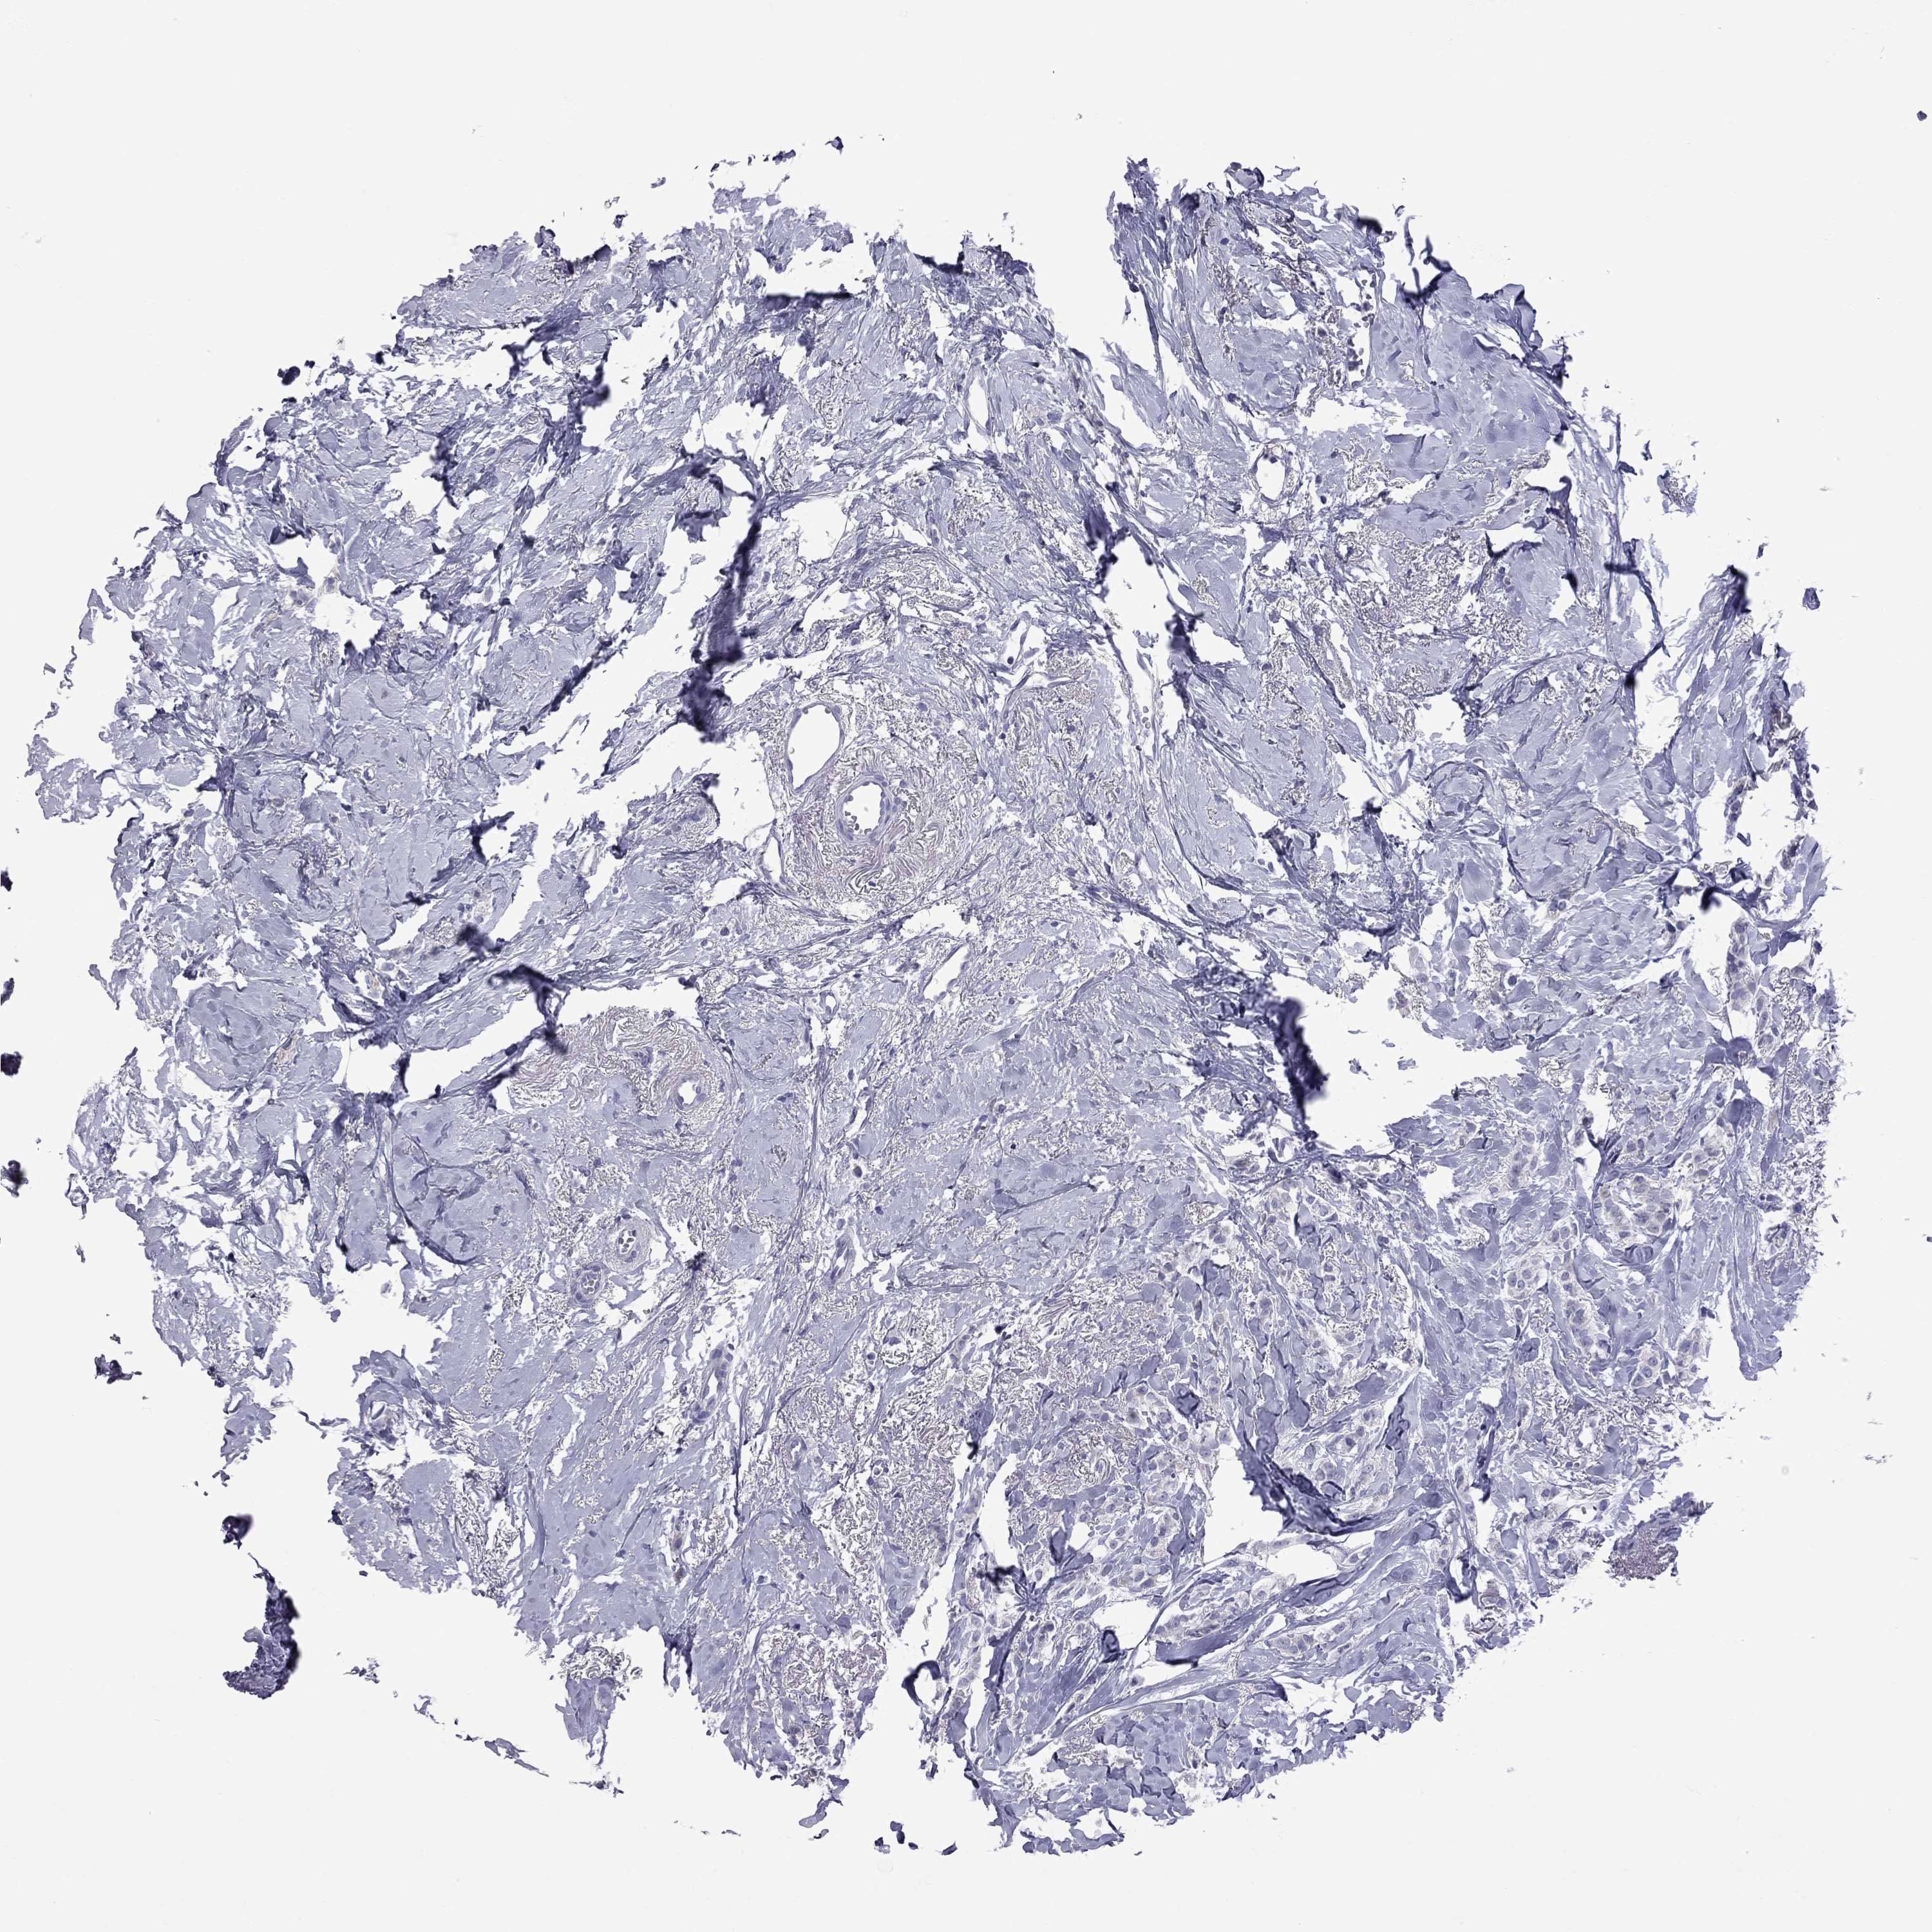

BRCA TCGA BRCA VALIDATION PROTEIN EXPRESSION